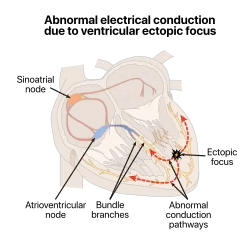

Sometimes a secondary pacemaker sets the pace, if the SA node is damaged or if the electrical conduction system of the heart has problems. Cardiac arrhythmias can cause heart block, in which the contractions lose their rhythm. In humans, and sometimes in other animals, a mechanical device called an artificial pacemaker (or simply "pacemaker") may be used after damage to the body's intrinsic conduction system to produce these impulses synthetically.

Ectopic pacemaker

An ectopic pacemaker also known as an ectopic focus or ectopic foci, is a group of excitable cells that causes a premature heart beat outside the normally functioning SA node of the heart. It is thus a cardiac pacemaker that is ectopic, producing an ectopic beat. If chronic this can result in arhythmias such as tachycardia, bradycardia, or ventricular fibrillation. An artificial pacemaker may be used to counter this.

A pacemaker is an artificial cardiac pacemaker, that is an implanted medical device that generates electrical impulses delivered by electrodes to the chambers of the heart either the upper atria, or lower ventricles to cause the targeted chambers to contract and pump blood. By doing so, the artificial pacemaker takes over from the primary SA node pacemaker to regulate the function of the heart's electrical conduction system.